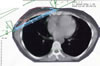

Mammakarzinom